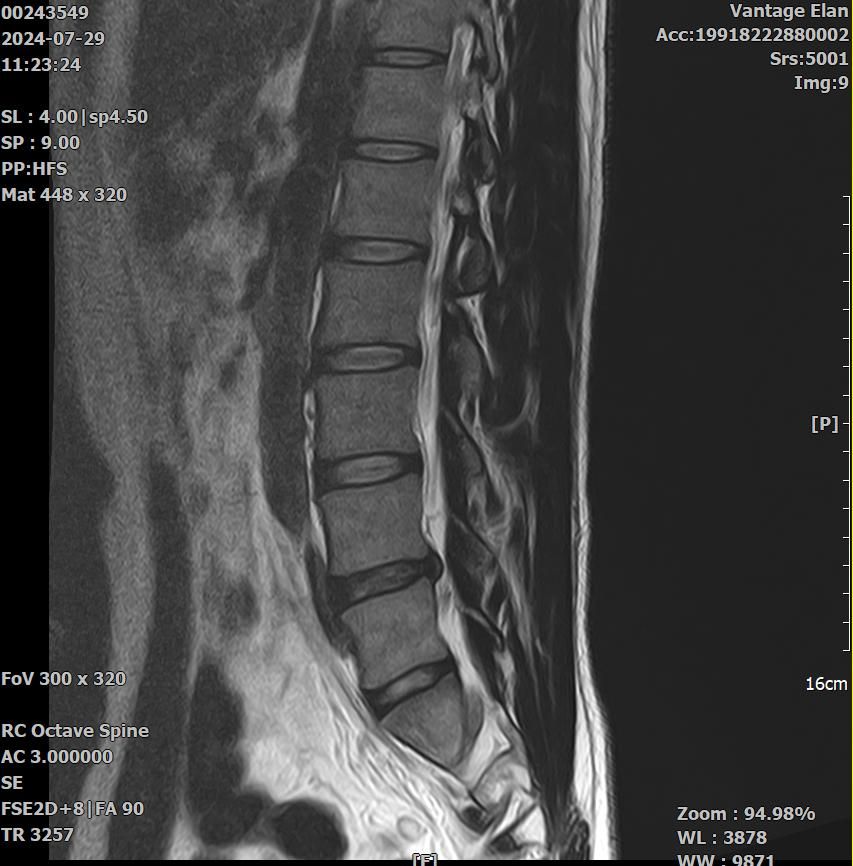

21년도와 24년도 각각 찍은 L spine 사진입니다.

2024년 영상